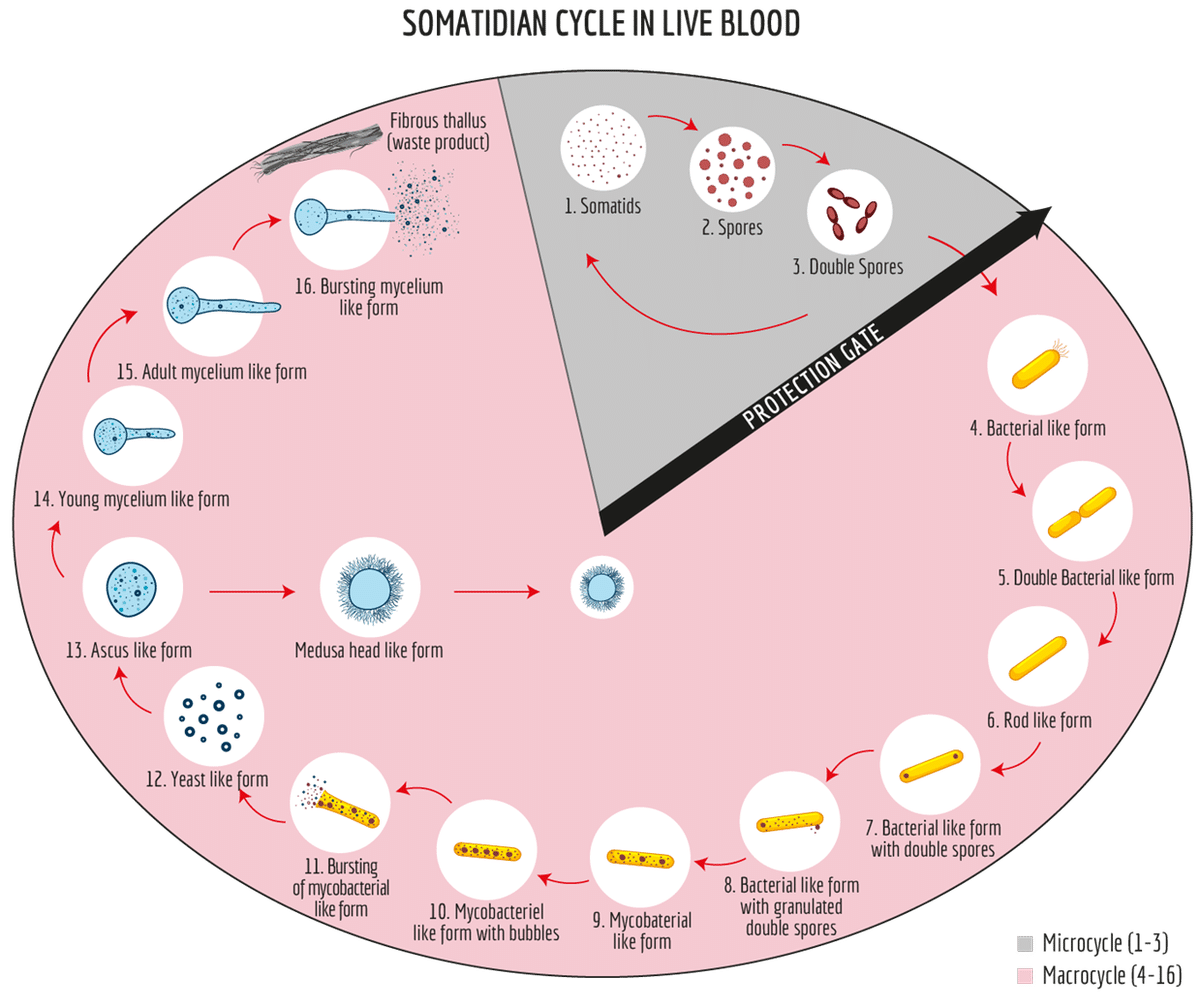

ネサンは、健康な人の血液中にうごめく極微小な生命体の存在を確認し、これをソマチッドと名付けた。そしてこのソマチッドが、成長に応じて16段階の変化をすることを発見した(ソマチッド・サイクル)。

健康な人のソマチッドは、上図の1から3の変化を繰り返しているが、血液環境の悪化により、この周期は破られ、4に突入する。ここから始まって、16まで、それぞれの段階において、それぞれの疾病像が現れる。

そこで、ネサンは、テラン(健康な血液内環境)の維持には、ソマチッドサイクルを1から3に留めることが重要であるとし、血液検査によって健康状態のスクリーニングが可能であると考えた。